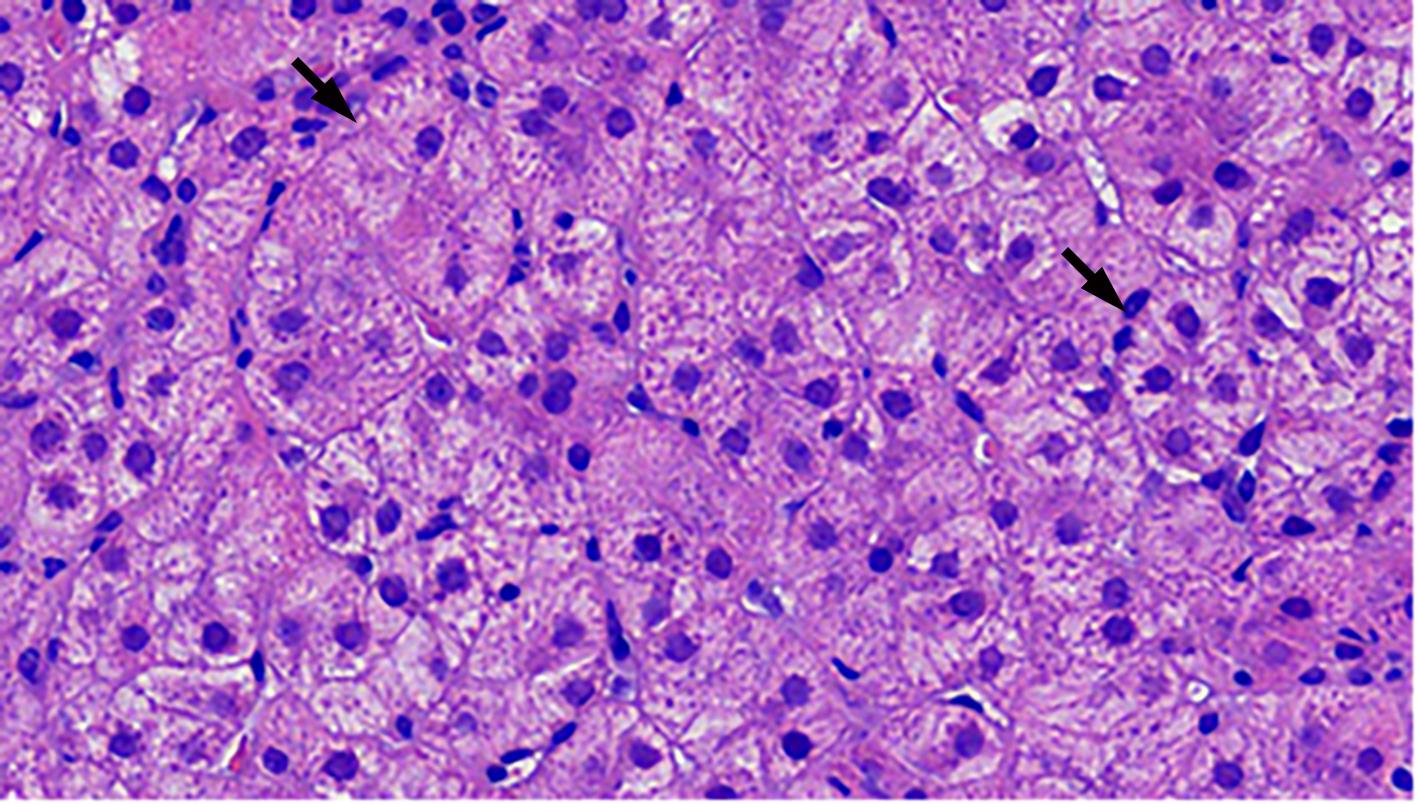

Autoimmune hepatitis (AIH) is an immune-mediated inflammatory disease of the liver parenchyma, which is characterized by hypergammaglobulinemia, the presence of autoantibodies, and typical abnormalities in liver histology; however, the diverse clinical manifestations of AIH and the lack of specific serological markers have brought difficulties and challenges in the diagnosis of AIH. Although portal lymphoplasmacytic infiltration, interface hepatitis, lymphocyte emperipolesis, and hepatocyte rosettes are the typical histological features of AIH, many other histological features can also be observed in AIH, including centrilobular necrosis and Kupffer cell hyaline globules. Therefore, no single histological feature can be used for the diagnosis of AIH, and a confirmed diagnosis should be made with reference to clinical and laboratory examinations, with the exclusion of liver diseases due to other causes. This article summarizes the histological features of AIH, different histopathological spectrum, common clinical issues, differential diagnosis, and recent advances.